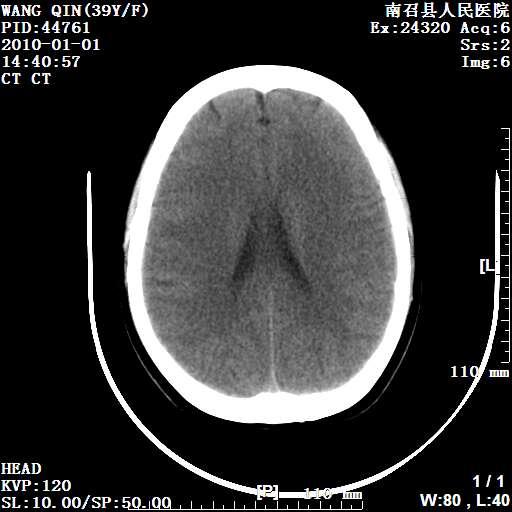

以下是引用随光逐影在2010-1-22 9:03:00的发言:[br]考虑左侧中颅窝(蝶骨翼区)脑膜瘤侵犯蝶骨翼并突入左侧眼眶。

以下是引用水过无痕在2010-1-22 14:55:00的发言:[br]一、定位:颅外占位;二、定性:恶性可能性大;三、组织来源:来源于左侧眼外直肌或其他部位;考虑为:横纹肌肉瘤>转移瘤>脑膜瘤.